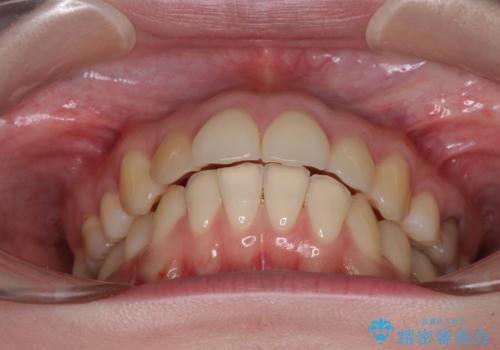

- 高校生の時に矯正治療を行ったものの、後取りをしてしまったとのことで来院された患者様です。

マウスピースでもワイヤー矯正でも対応可能でしたが、再度ワイヤーは装着したくないとのことでインビザラインにて矯正治療を行うこととしました。

インビザラインは長時間装着するための自己管理が極めて重要であり、自信はあまりないとのことでしたが、インビザラインを選択されました。

舌の突出癖が原因で後戻りをしたため、舌のトレーニングをしっかりと行っていただき、口元の突出感を改善することができました。

インビザラインの装着時間が守れず、1年強で終わる予定でしたが、4年間を要することとなりました。